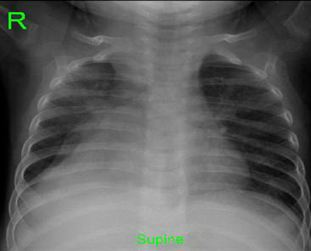

Penetrating Rectal Trauma: Laparoscopic Management without Fecal Diversion

Drahos A*, Nolan HR, Bozeman A